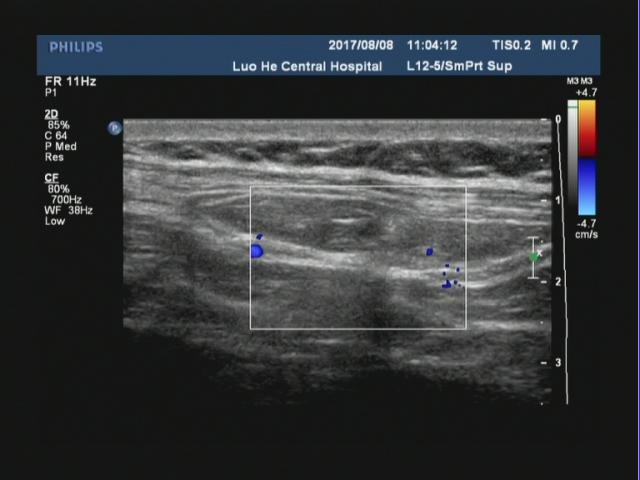

腹壁切口疝指临床体检可触及或影像学检查可显示的原手术切口下的腹壁缺损,是腹部外科手术后的常见并发症,常发生于年老体弱患者可伴或不伴腹壁包块,发病率通常为2%~11%。切口疝无法自愈,可引起患者不适或导致腹腔内容物绞窄。二维超声可直观了解疝环的大小、形态及深度,疝囊大小、位置,疝内容物及疝囊疝出和回纳途径。

对于切口疝二维超声扫描不仅能够清晰显示自皮肤表层到腹壁深层的解剖学全貌,还可直观显示切疝环的大 小、形态及深度,疝囊大小、位置及疝内容物。通过嘱患者用力咳嗽增加腹压或改变体位等方法,超声可实时动态显示疝囊由筋膜缺损处疝出以及回纳的过程。但随着腹壁外科的不断进展和疝修补技术的多样化,外科医师术前需要了解更具体的信息。以往研究认为二维灰阶超声可以检出所有切口疝。但当切口疝的缺损范围较大或存在多发性切口疝时,受小器官探头长度限制,二维灰阶超声存在测量数据明显偏小和病灶检出率明显降低等问题。因此我们可以采用现在新机器上的宽景成像技术,通过连续扫描与拼接图像,不仅可以在同一幅图像上显示较大范围的病灶并进行测量,还可显示周围相邻组织的情况。因此我们要会用、善用新软件,宽景成像不仅可对腹壁切口疝进行容积扫描,明显提高疝气病灶的检出率,客观显示整个切口疝的全貌,准确测量疝囊的大小,为临床医师对切口疝的分类提供准确数据;还可以显示二维超声所不能显示的冠状面图像,更准确地测量疝环,为临床医师选择疝修补术手术方式和决定补片大小提供具体精确的数据。